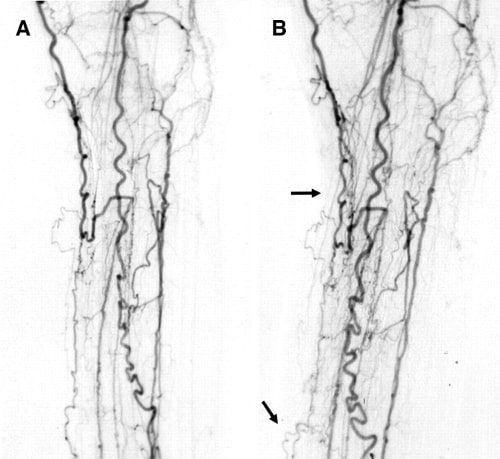

Изображения, связанные с атеросклерозом нижних конечностей и его лечением